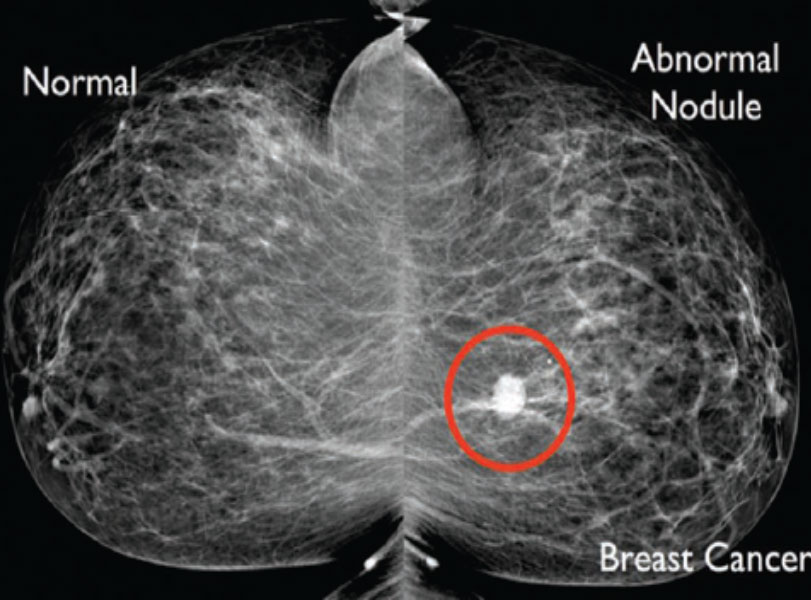

பொதுவாக மார்பக கட்டிகளில் 80% சாதரண கட்டிகள் ஆகும், 20 % களில் மட்டுமே புற்றுநோய் கட்டிகள் ஆகும்.

மருத்துவ பரிசோதனை - Medical Examination

மருத்துவரின் (Clinical Examination) பரிசோதனை.

கதிரியக்க பரிசோதனை (Radiological Assessment).

செவியிணரா ஒலி மற்றும் மேம்மோகிராம் எனப்படும் அதி நவீன எக்ஸ்ரே உதவி கொண்டு மார்பக கட்டிகள் பரிசோதிக்கப்படுகிறது.

மார்பக கட்டி அணுக்கள் பரிசோதனை (Fine Needle Aspiration Cytology , Trucut Biopsy )

மார்பக கட்டிகளில் செல்கள் மற்றும் திசுக்கள் ஊசி மூலம் எடுக்கப்பட்டு நோய் குறியியல் மருத்துவரால் பரிசோதிக்கப்படுகிறது.